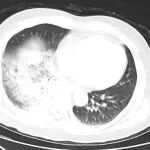

双肺全白,抢救12天…医生提醒:早期症状似感冒

近期广东惠州一名中年女性因持续高热、气喘被紧急送医双肺全白,生命危在旦夕经过12天的抢救才脱离危险而这一切竟与家中的鹦鹉有关图源:视觉中国经医院证实这场疾病的元凶是“鹦鹉热”鹦鹉热不仅鹦鹉有鹦鹉热是一